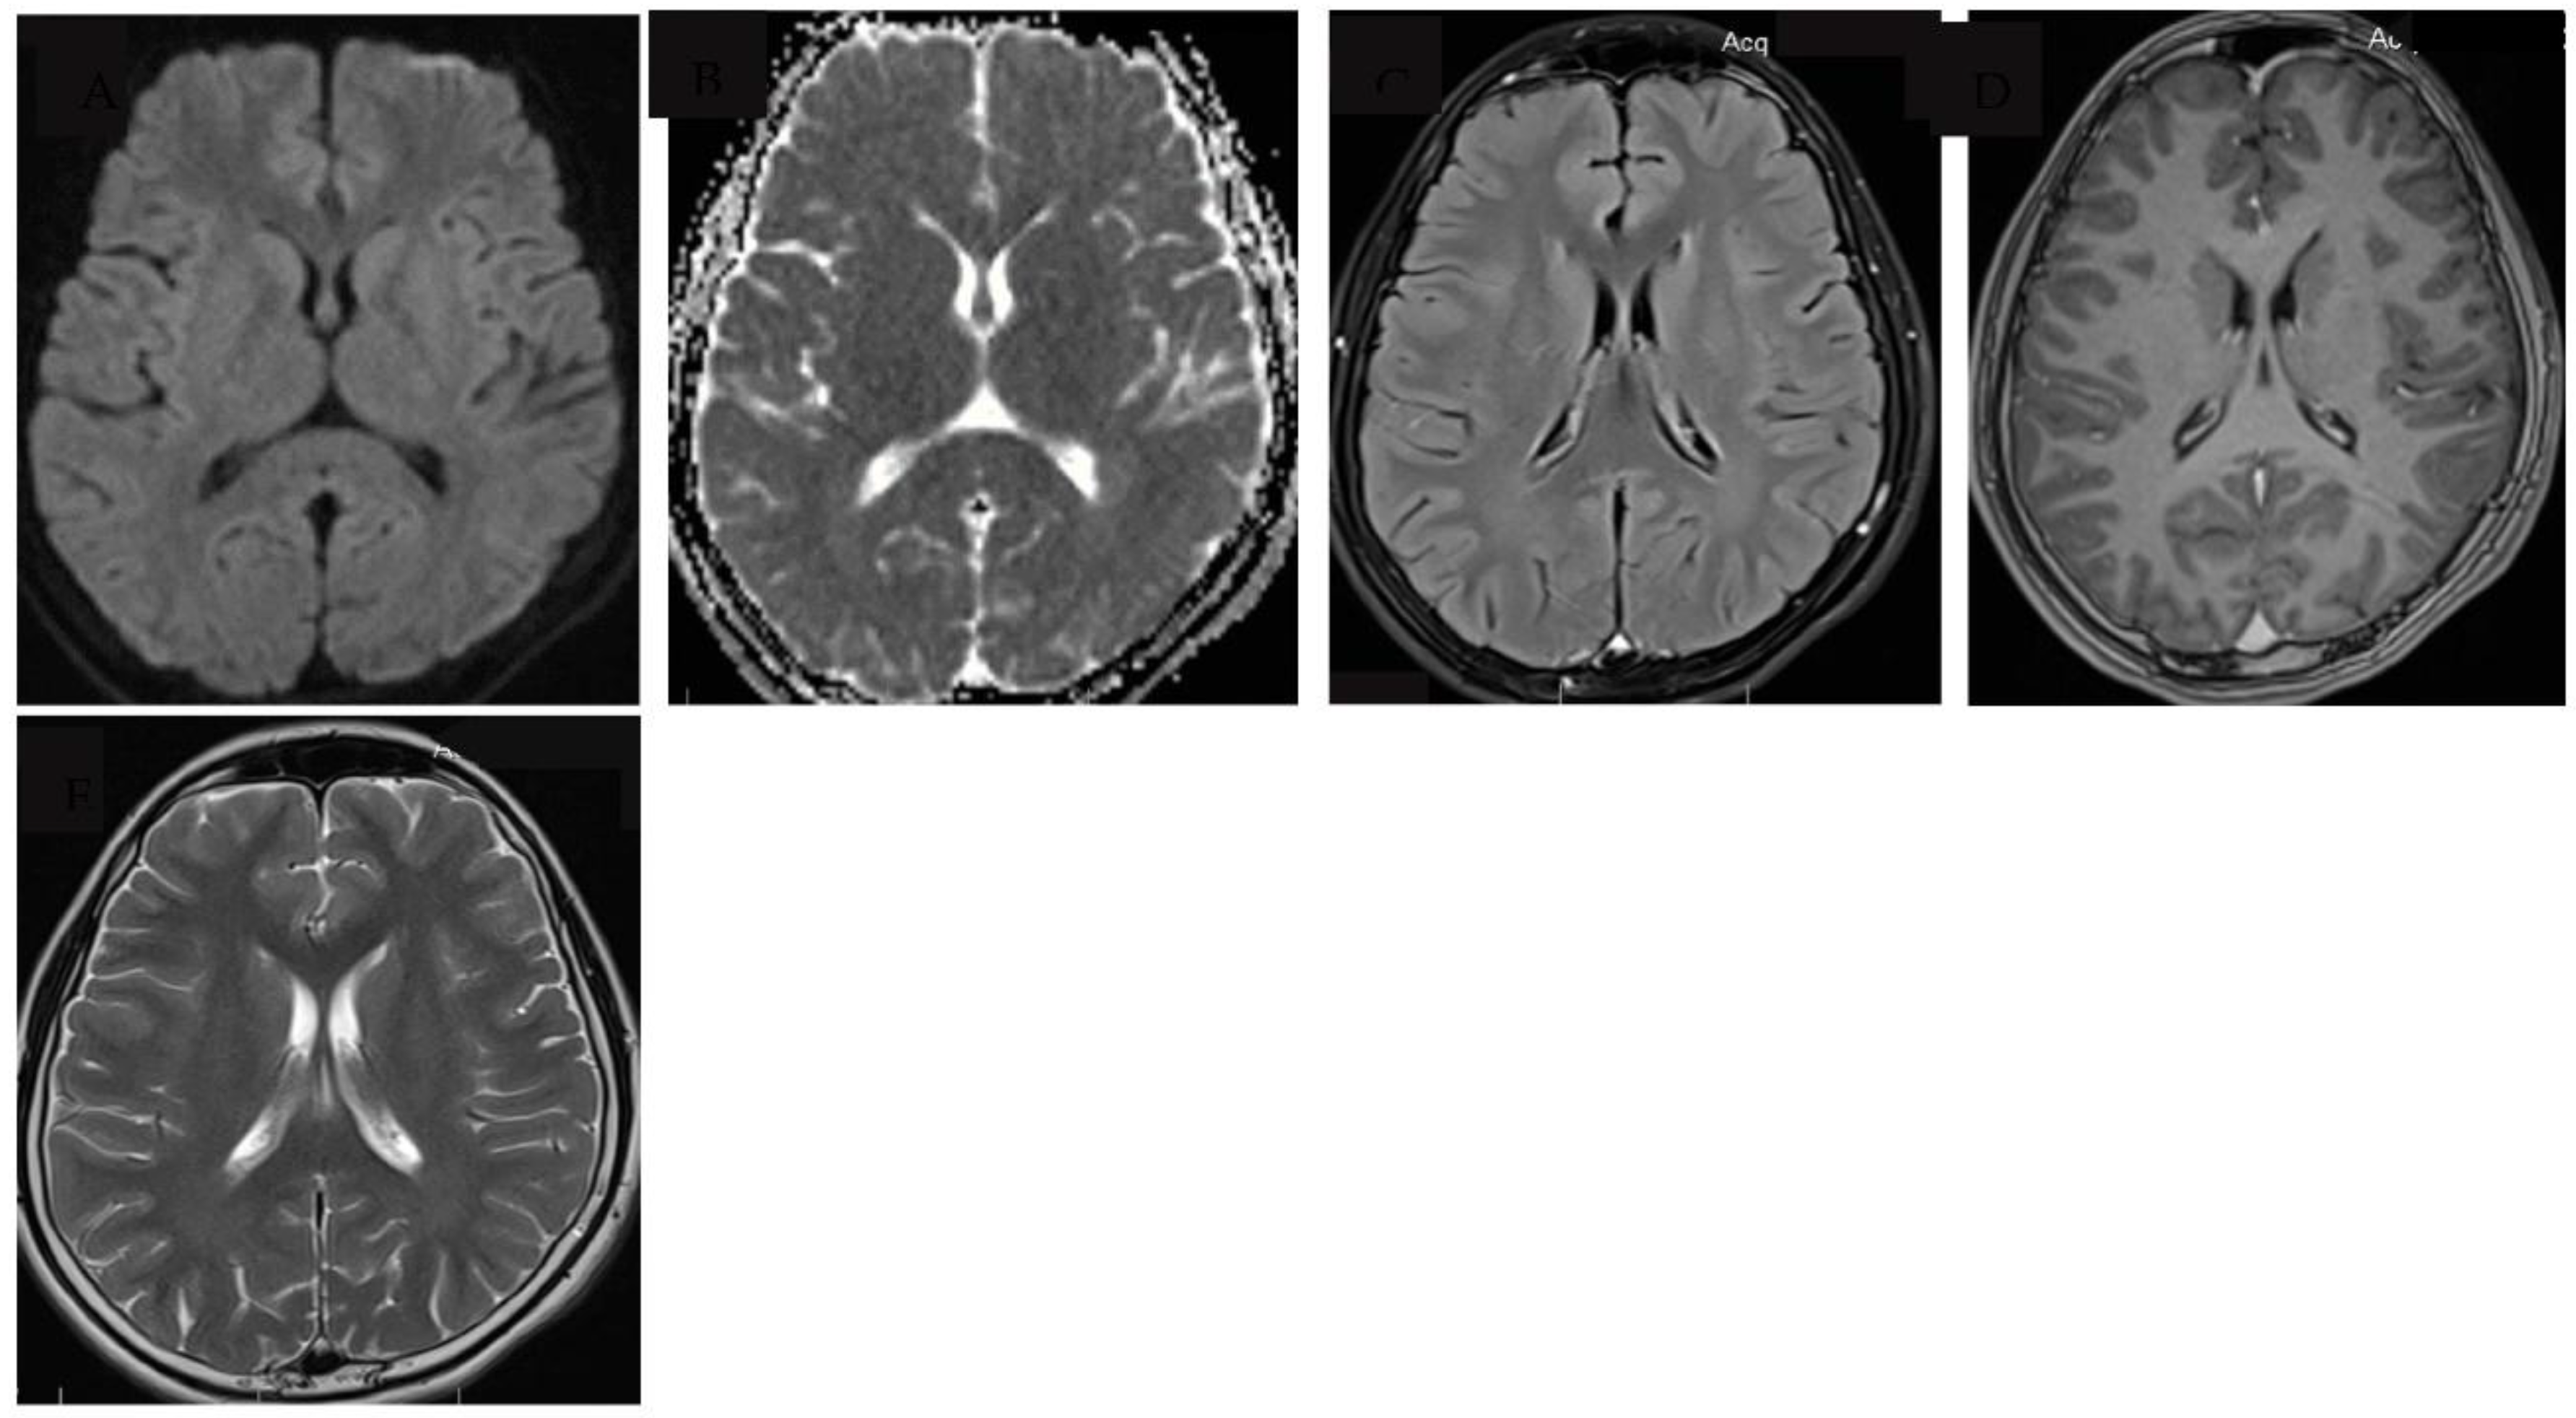

Tuberculous meningitis (TBM) is the most severe form of tuberculosis, disproportionately affecting vulnerable populations such as young children and people living with human immunodeficiency virus (HIV). Major challenges to accurate and early diagnosis of TBM are the non-specific clinical features which overlap with other infectious syndromes and the lack of adequately sensitive tests to detect Mycobacterium Tuberculosis in the cerebrospinal fluid (CSF). Diagnosis is therefore still dependent on clinical suspicion along with clinical features, cerebrospinal fluid (CSF) characteristics and where facilities are available, neuroimaging. Typical neuroimaging features of TBM include hydrocephalus, infarcts, tuberculomas and basal exudates, however less well described are very rare features such as cytotoxic lesion of the corpus callosum (CLOCC) otherwise known as transient splenic lesion. We describe the first case report of a child with confirmed TBM who had a very rare presentation of CLOCC, present a literature review on the pathophysiology and alternative aetiologies where CLOCC is more commonly seen.